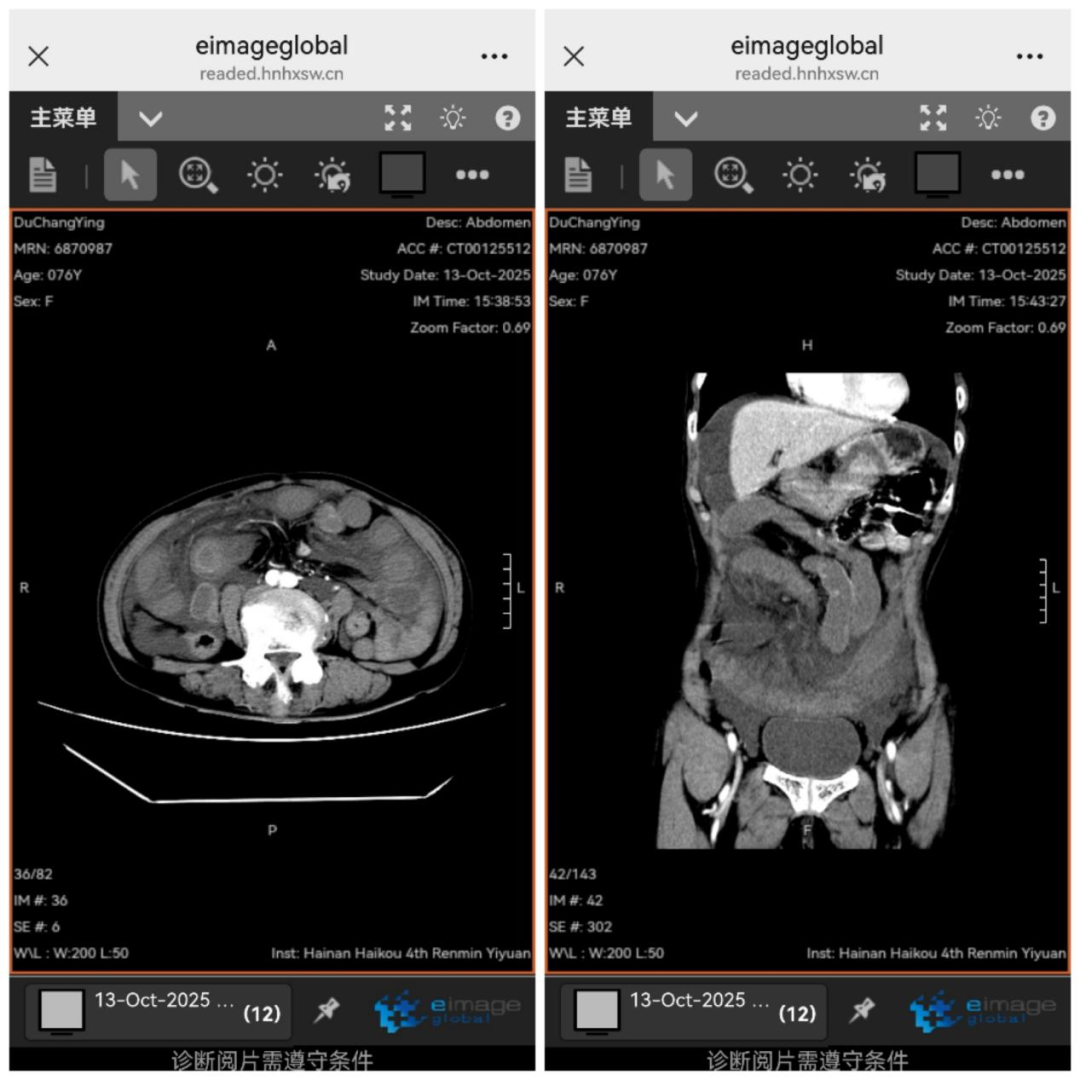

家人立即将杜奶奶送至我院急诊科。入院时,她生命体征极不稳定,收缩压超190mmHg,心率仅45次/分,仍间歇性剧烈腹痛。急诊科林亚发主任迅速指导救治,并紧急邀请普通外科会诊。经腹部CT及双次心电图、心肌酶检查,排除急性心梗、腹主动脉夹层后,将杜奶奶收治至普通外科。

入科后,普通外科刘琪主任仔细检查,发现患者突发剧烈腹痛、腹肌软、中下腹部压痛、无明显腹胀,起病时间短,无典型肠梗阻症状。与放射科共同阅片后,考虑小肠肠管水肿,刘琪主任判断闭袢性小肠梗阻可能性极大,同时稳定患者生命体征,立即安排腹部增强CT检查。

检查显示,患者腹部积液快速增多,肠管扩张增厚。刘琪主任指出病情急剧恶化,疼痛可能引发疼痛性休克,体液快速丢失会导致失血性休克,肠道坏死细菌外移,坏死组织释放的炎性介质会冲击多脏器功能。时间紧迫,必须立即手术探查。随后,麻醉科蔡弥松主任、重症医学科吴清松主任应邀协诊,共同制定围手术期治疗方案。在患者家属充分信任下,手术迅速展开。